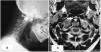

Case descriptionA 64-year-old man with a history of urolithiasis and with no family history of inflammatory rheumatism, was followed in pneumology department for a chronic cough and recurrent bronchitis, diagnosed as diffuse infiltrating pneumopathy. The patient also complained of an eight-year history of isolated inflammatory neck pain which is not improved by paracetamol or rest, but partially improved by non-steroidal drugs. He denied additional musculoskeletal manifestations. Vital signs were normal as well as chest, abdomen and limb examinations. The neck examination was normal apart from pressure pain in the cervical spine. The musculoskeletal examination was without any abnormalities in particular, there were neither synovitis nor pain at the joints pressure. The neurological examination was normal. X ray of the cervical spine showed C1–C2 diastasis and magnetic resonance imaging (MRI) showed a C1–C2 arthritis, an edematous pannus, an atlantoaxial subluxation with a C1–C2 distance at 4.6mm, the absence of basilar impression and the absence of morphological or spinal cord signal abnormality (Fig. 1).